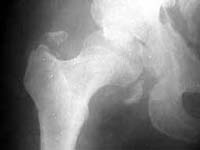

Seeking advice on management of 50 years old male who presented with infected fracture dislocation right hip with complete sciatic nerve palsy three months after injury. Xrays initial and current and CT scan Current images attached.

AP 3 mos ago